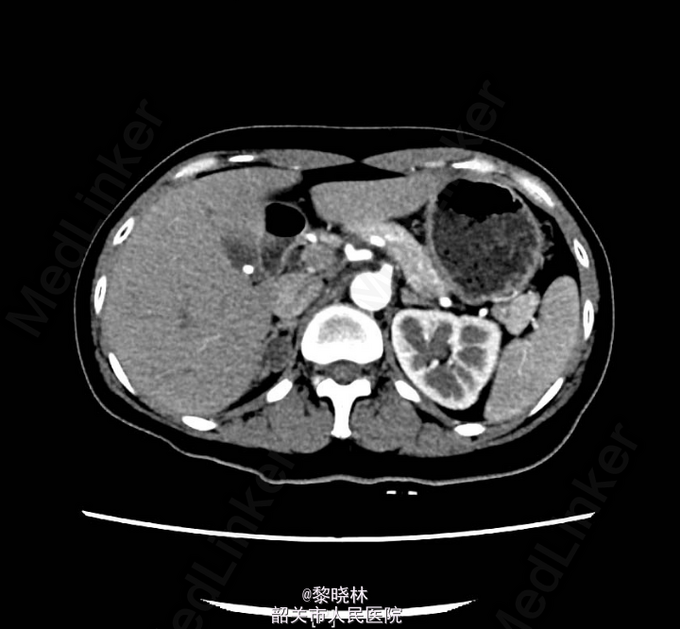

入院查体:BP182/111mmHg,余无特殊。辅助检查门诊CT示双肾+肾上腺螺旋CT平扫+增强扫描(中腹)检查所见:1、右肾上腺结节,考虑腺瘤;左肾上腺增生。2、左肾下盏结石。3、小副脾。

诊断:高血压查因:肾上腺瘤? 入院后查尿蛋白定量/尿肌酐比值 尿总蛋白0.030g/L,尿肌酐4019.000umol/L。高血压三项 醛固酮547.930pg/ml,肾素浓度23.520pg/ml,血管紧张素II137.070pg/ml。 血清钾、钠、氯测定 钾2.930mmol/L。血常规、尿常规、大便常规、生化、甲功、肿瘤标志物、胸片、心电图均未见明显异常。排除手术禁忌症后,于2015-03-16行右侧后腹腔镜下肾上腺肿物切除术,术后病理提示“右侧肾上腺皮质腺瘤”。